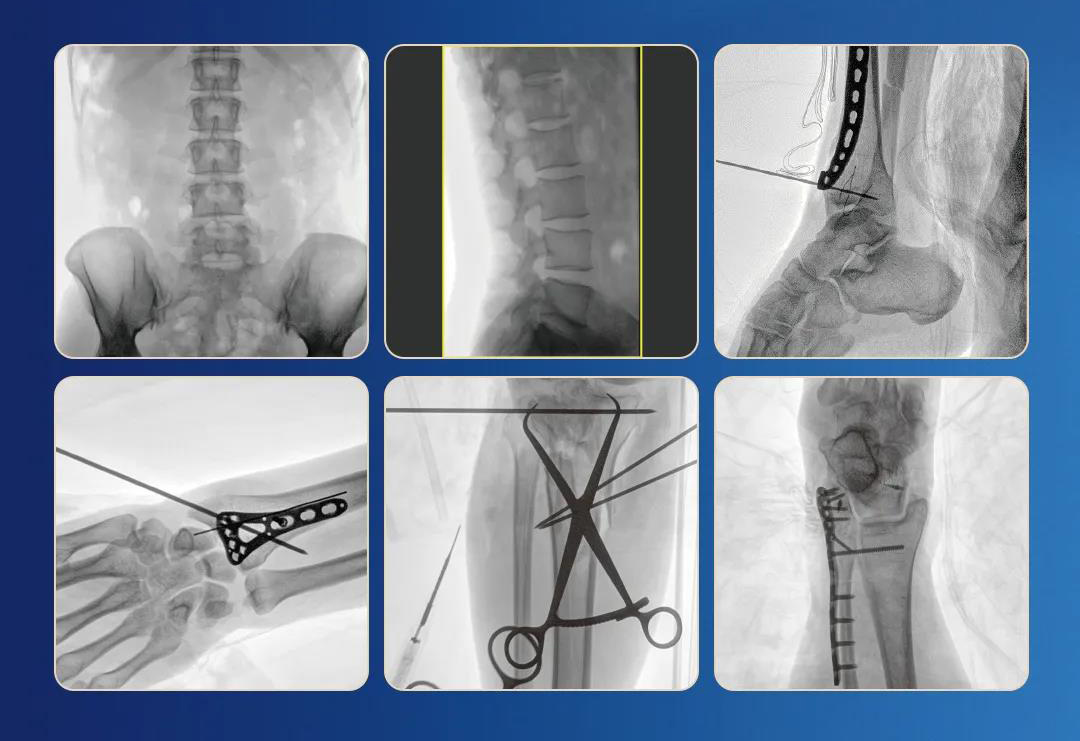

一、临床应用

1.关节手术

2.创伤手术

3.脊柱手术

4.疼痛治疗